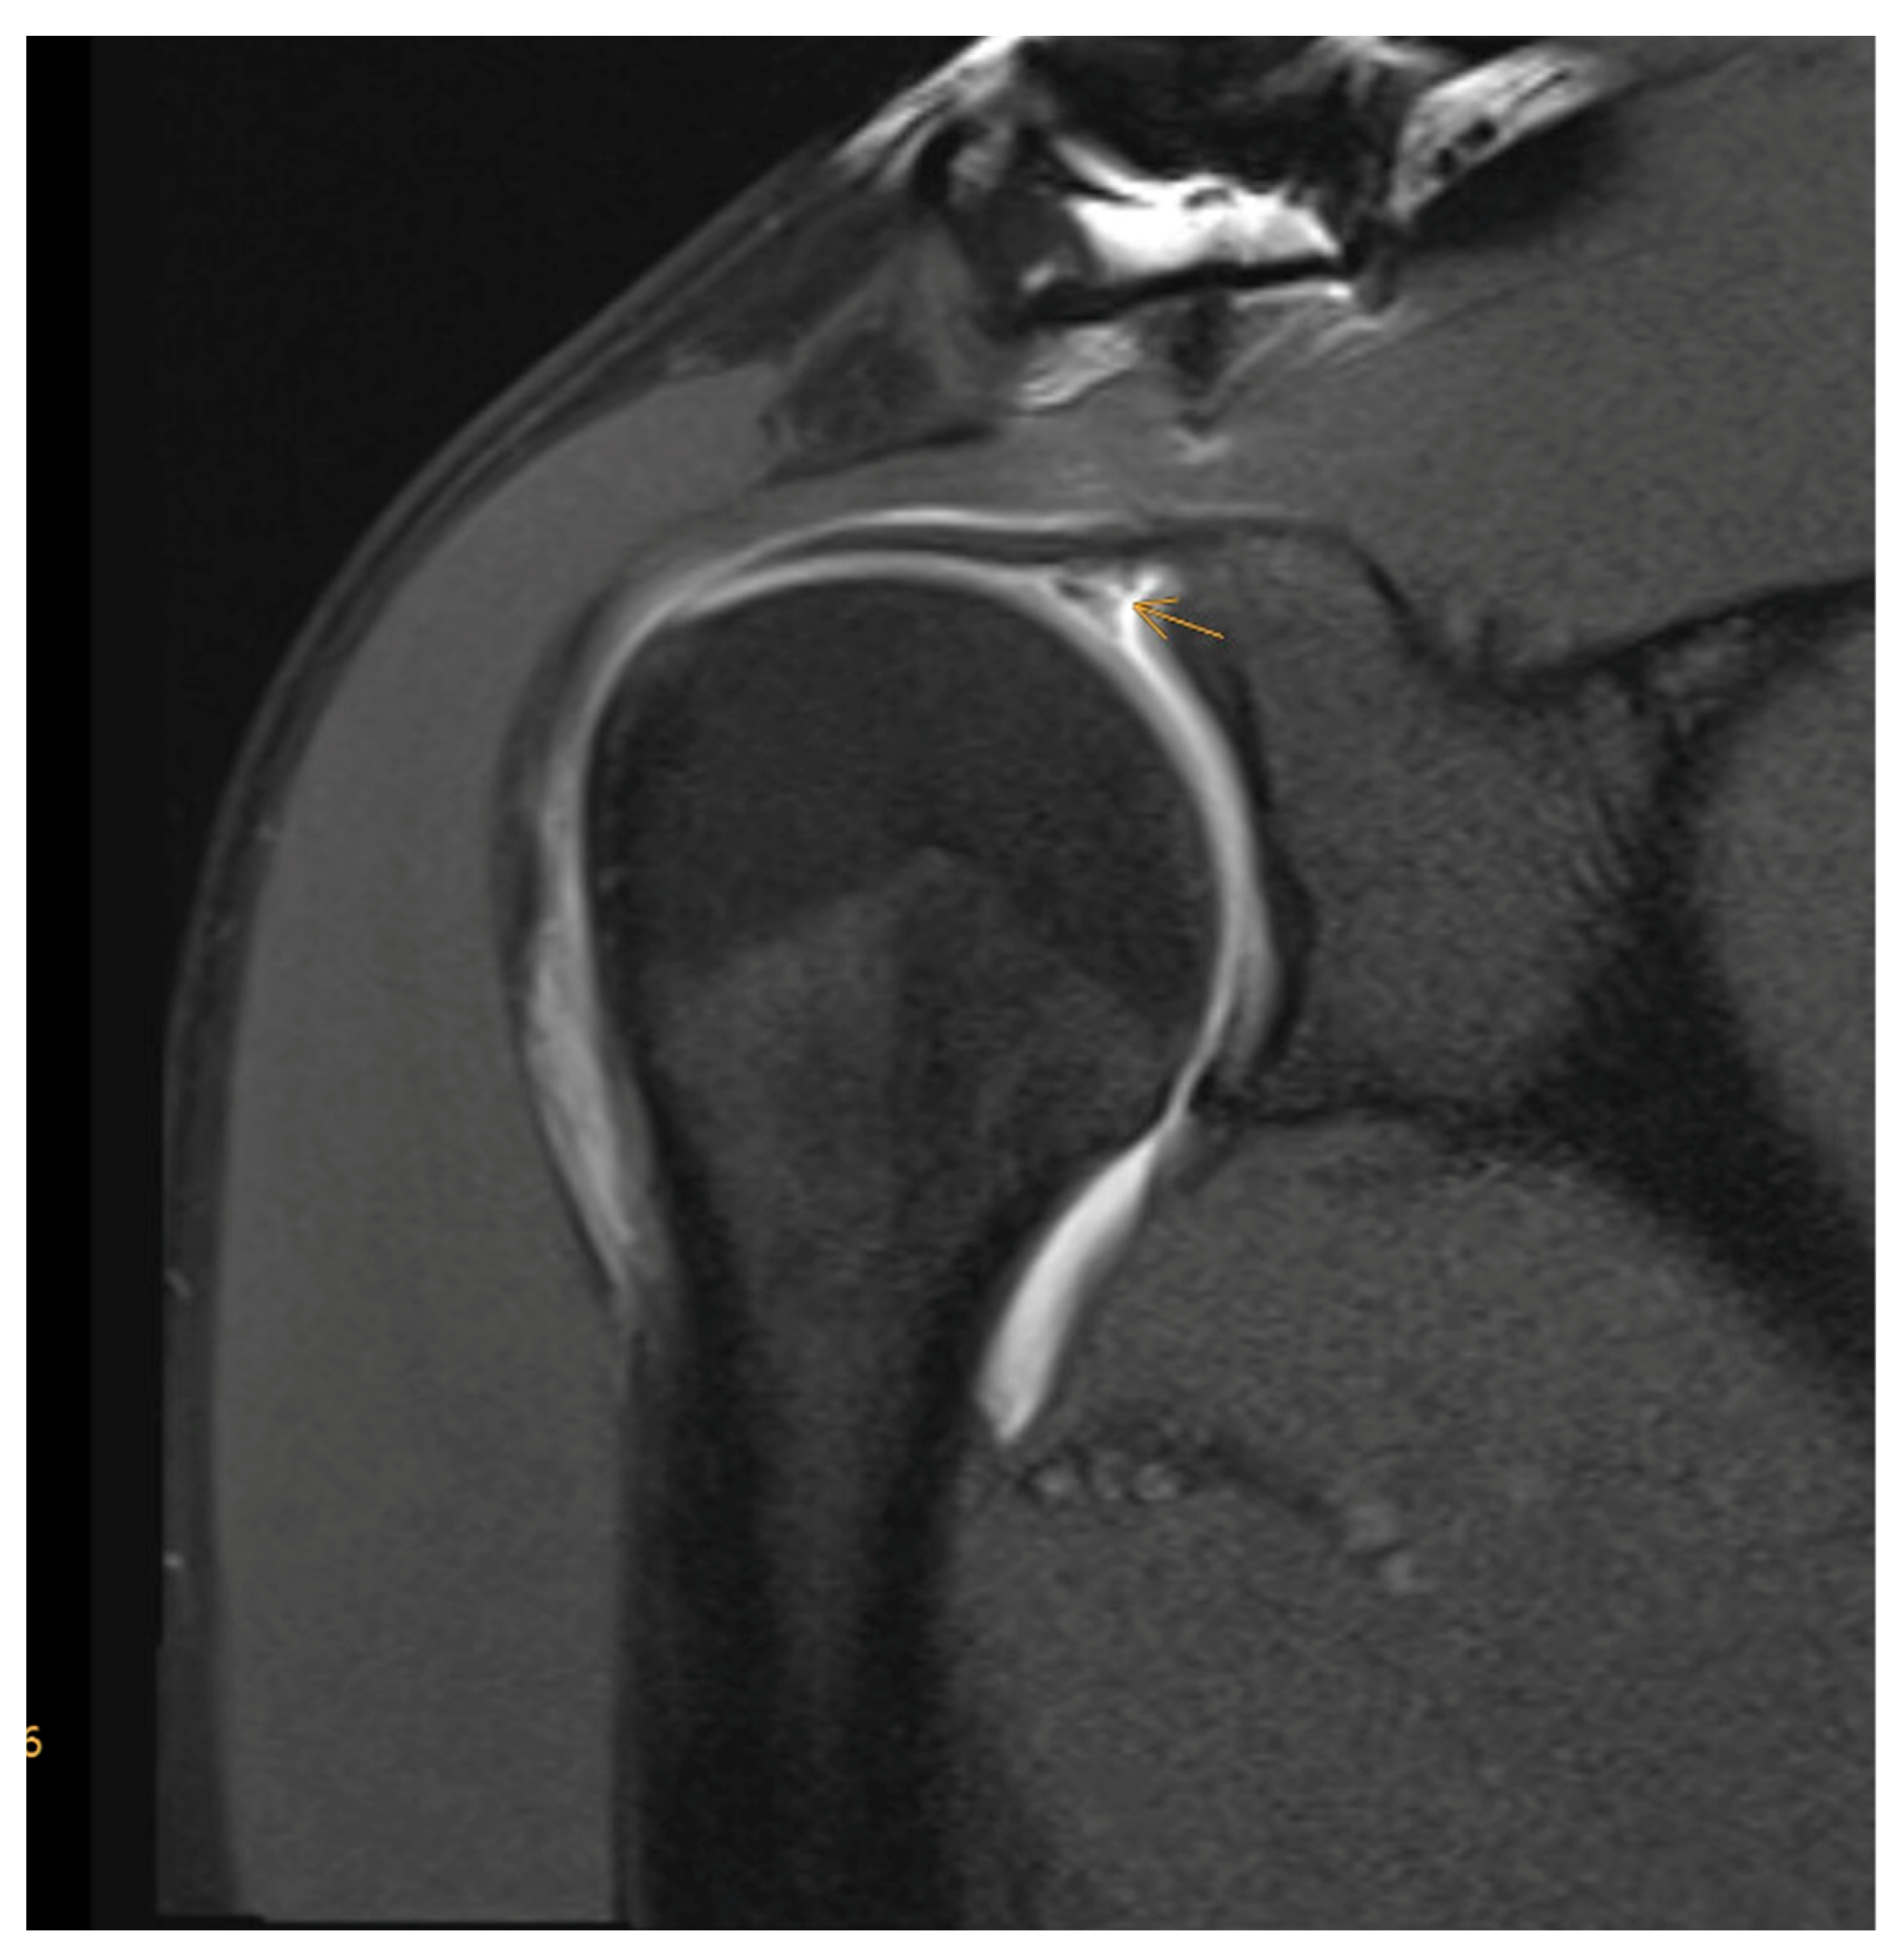

- Meyer, D.C.; Wieser, K.; Farshad, M.; Gerber, C. Retraction of Supraspinatus Muscle and Tendon as Predictors of Success of Rotator Cuff Repair. Am. J. Sports Med. 2012, 40, 2242–2247. [Google Scholar] [CrossRef]

- Fuchs, B.; Weishaupt, D.; Zanetti, M.; Hodler, J.; Gerber, C. Fatty degeneration of the muscles of the rotator cuff: Assessment by computed tomography versus magnetic resonance imaging. J. Shoulder Elb. Surg. 1999, 8, 599–605. [Google Scholar] [CrossRef] [PubMed]

- Goutallier, D.; Postel, J.M.; Bernageau, J.; Lavau, L.; Voisin, M.C. Fatty muscle degeneration in cuff ruptures. Pre- and postoperative evaluation by CT scan. Clin. Orthop. Relat. Res. 1994, 304, 78–83. [Google Scholar] [CrossRef]